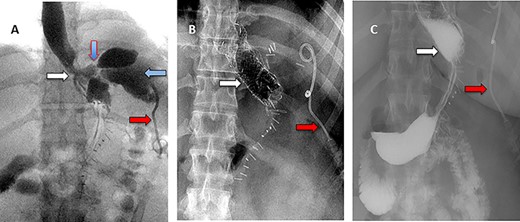

A 36-year-old obese female patient underwent a sleeve gastrectomy abroad. Eleven days after surgery, she presented with an abdominal pain. Abdominal computer tomography (CT) revealed several fluid-air collections (3 abscesses) around the upper greater gastric curve (3.5 × 3.2 cm), lesser sac (7 × 3.3 cm) as well as anterior to the spleen (7 × 3.3 cm). By that time, there was also left pleural effusion and atelectasis of the left lower lung lobe. On the next day, CT-guided aspiration was done (Fig. 1) and a pigtail catheter was inserted to drain the abscesses. On the following day, water-soluble oral contrast displayed an active contrast leak along the proximal sleeve gastrectomy (Fig. 2). On the same day, covered esophageal stent was placed endoscopically. The patient was discharged home and was scheduled for stent removal after 2 weeks. However, after 2 days, the patient presented again with an abdominal pain. The plain x-ray showed slippage of the stent distally. Upper GI endoscopy was done, and the esophageal stent was removed. One day later, the patient condition deteriorated with a massive upper GI bleeding. A CT angiography showed no extravasation and the source of bleeding was not identified during endoscopy due to massive bleeding. An immediately performed angiogram revealed an AEF (Fig. 3). The interventional radiologist achieved transient cessation of the bleeding through embolization of the fistula with interlock coils (Fig. 3). An aortogram showed continuous extravasation of contrast through the fistula, and therefore, endovascular intervention was performed with implantation of 22 mm × 112 mm aortic stent (TEVAR using Valiant covered stent - Medtronic company, USA). One week after TEVAR, another long esophageal stent was positioned (from lower esophagus to the stomach). Two weeks later, a barium swallow proved no evidence of contrast leak. Then, the esophageal stent was removed, and the patient was discharged home. There was a plan for definitive reconstruction procedure, including removal of the endovascular stent and use of reconstructed pericardial bovine graft, however, the patient declined. About 10 months later, she presented with another attack of massive hematemesis, with a drop of hemoglobin to 8 g/dl and a blood pressure of 66/44 mmHg requiring a rapid sequence induction and infusion of packed red blood cells. An immediate abdominal CT showed evidence of peri-stent infection with no contrast extravasation. Upper GI endoscopy showed an evidence of an ischemic ulcer above the Z-line with granulation tissue at the ulcer edge and erosion of the endovascular stent into the lower esophagus. The patient had a positron emission tomography (PET) scan and diagnosed with mediastinitis due to aortic stent infection and septic shock (Fig. 4). Surgical intervention was offered but the patient declined. Treatment with broad spectrum antibiotics and blood transfusion were administrated as required. Around 5 weeks later, the patient developed massive upper GI bleeding requiring intubation and surgical intervention (distal esophagectomy with removal of the endovascular stent and resection and replacement of the AEF site with reconstructed tube using 14 × 9 cm bovine pericardial graft through left thoraco-abdominal incision utilizing left cardiopulmonary bypass and distal perfusion through left femoral artery (Fig. 5). Closure of the stomach with gastrostomy tube insertion for feeding had been performed. One and half year later, reconstruction surgery of the esophagus with colonic interposition was done. After 3-year follow-up, the patient was doing well with no complication.

(A) Aortography showed active contrast extravasation to the esophagus trough the fistula. (B) Coli embolization of the AEF with contrast beyond the coil. (C) Esophagogastroduodenoscopy revealed the site of the fistula and the coil embolization in the stomach. (D) An esophageal stent was placed extending to the stomach and the aortic stent in place. Feeding tube in place.